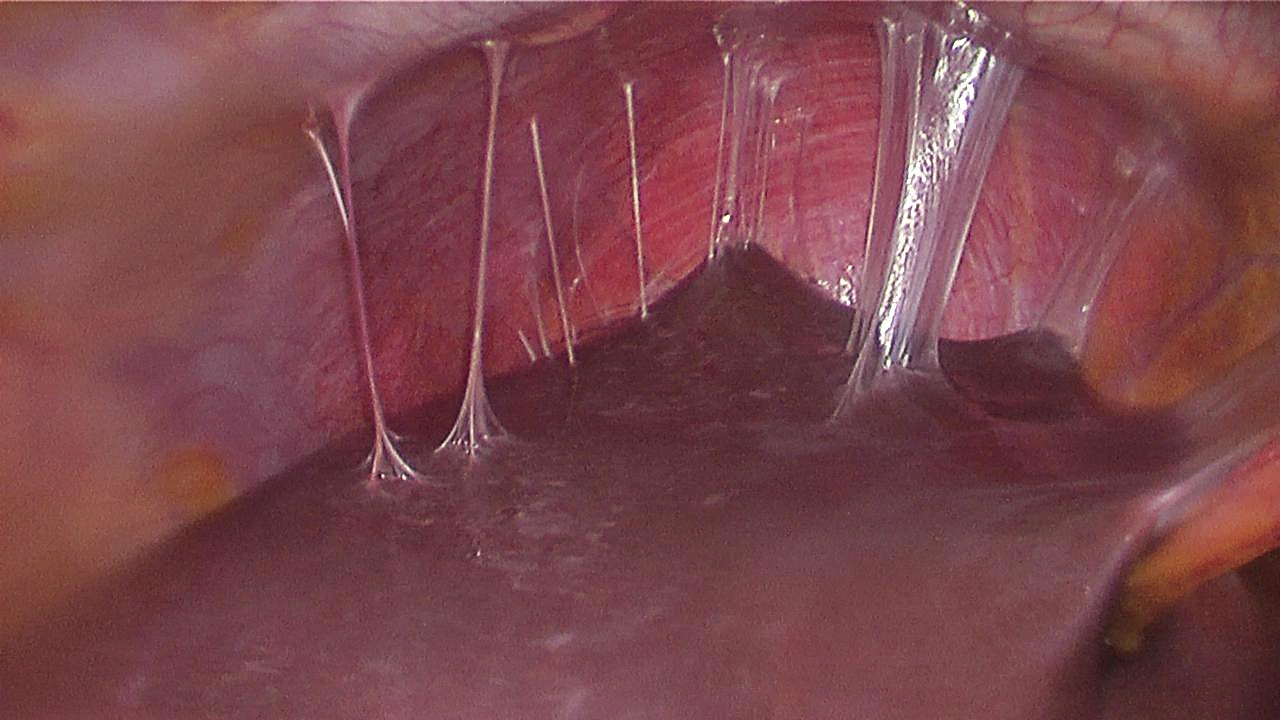

골반 검사에서 자궁경부 압통, 자궁 또는 부속기 압통이 나타난다.[1] 점액성 농성 자궁경부염 및/또는 요도염이 관찰될 수 있다. 심한 경우에는 복강경 검사, 복강 내 세균 채취 및 배양, 조직 생검과 같은 더 많은 검사가 필요할 수 있다.[22][23]복강경 검사를 통해 Fitz-Hugh–Curtis 간주위염과 기타 농양의 특징인 "바이올린 현" 유착을 시각화할 수 있다.